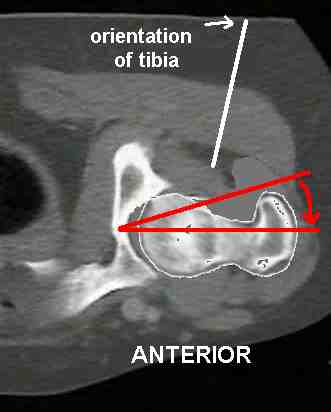

The examiner rotates the femur internally, moving the trochanter anteriorly until it protrudes laterally to the largest extent palpable. In this position, the goniometric measurement of hip internal rotation reflects the degree of femoral antetorsion.